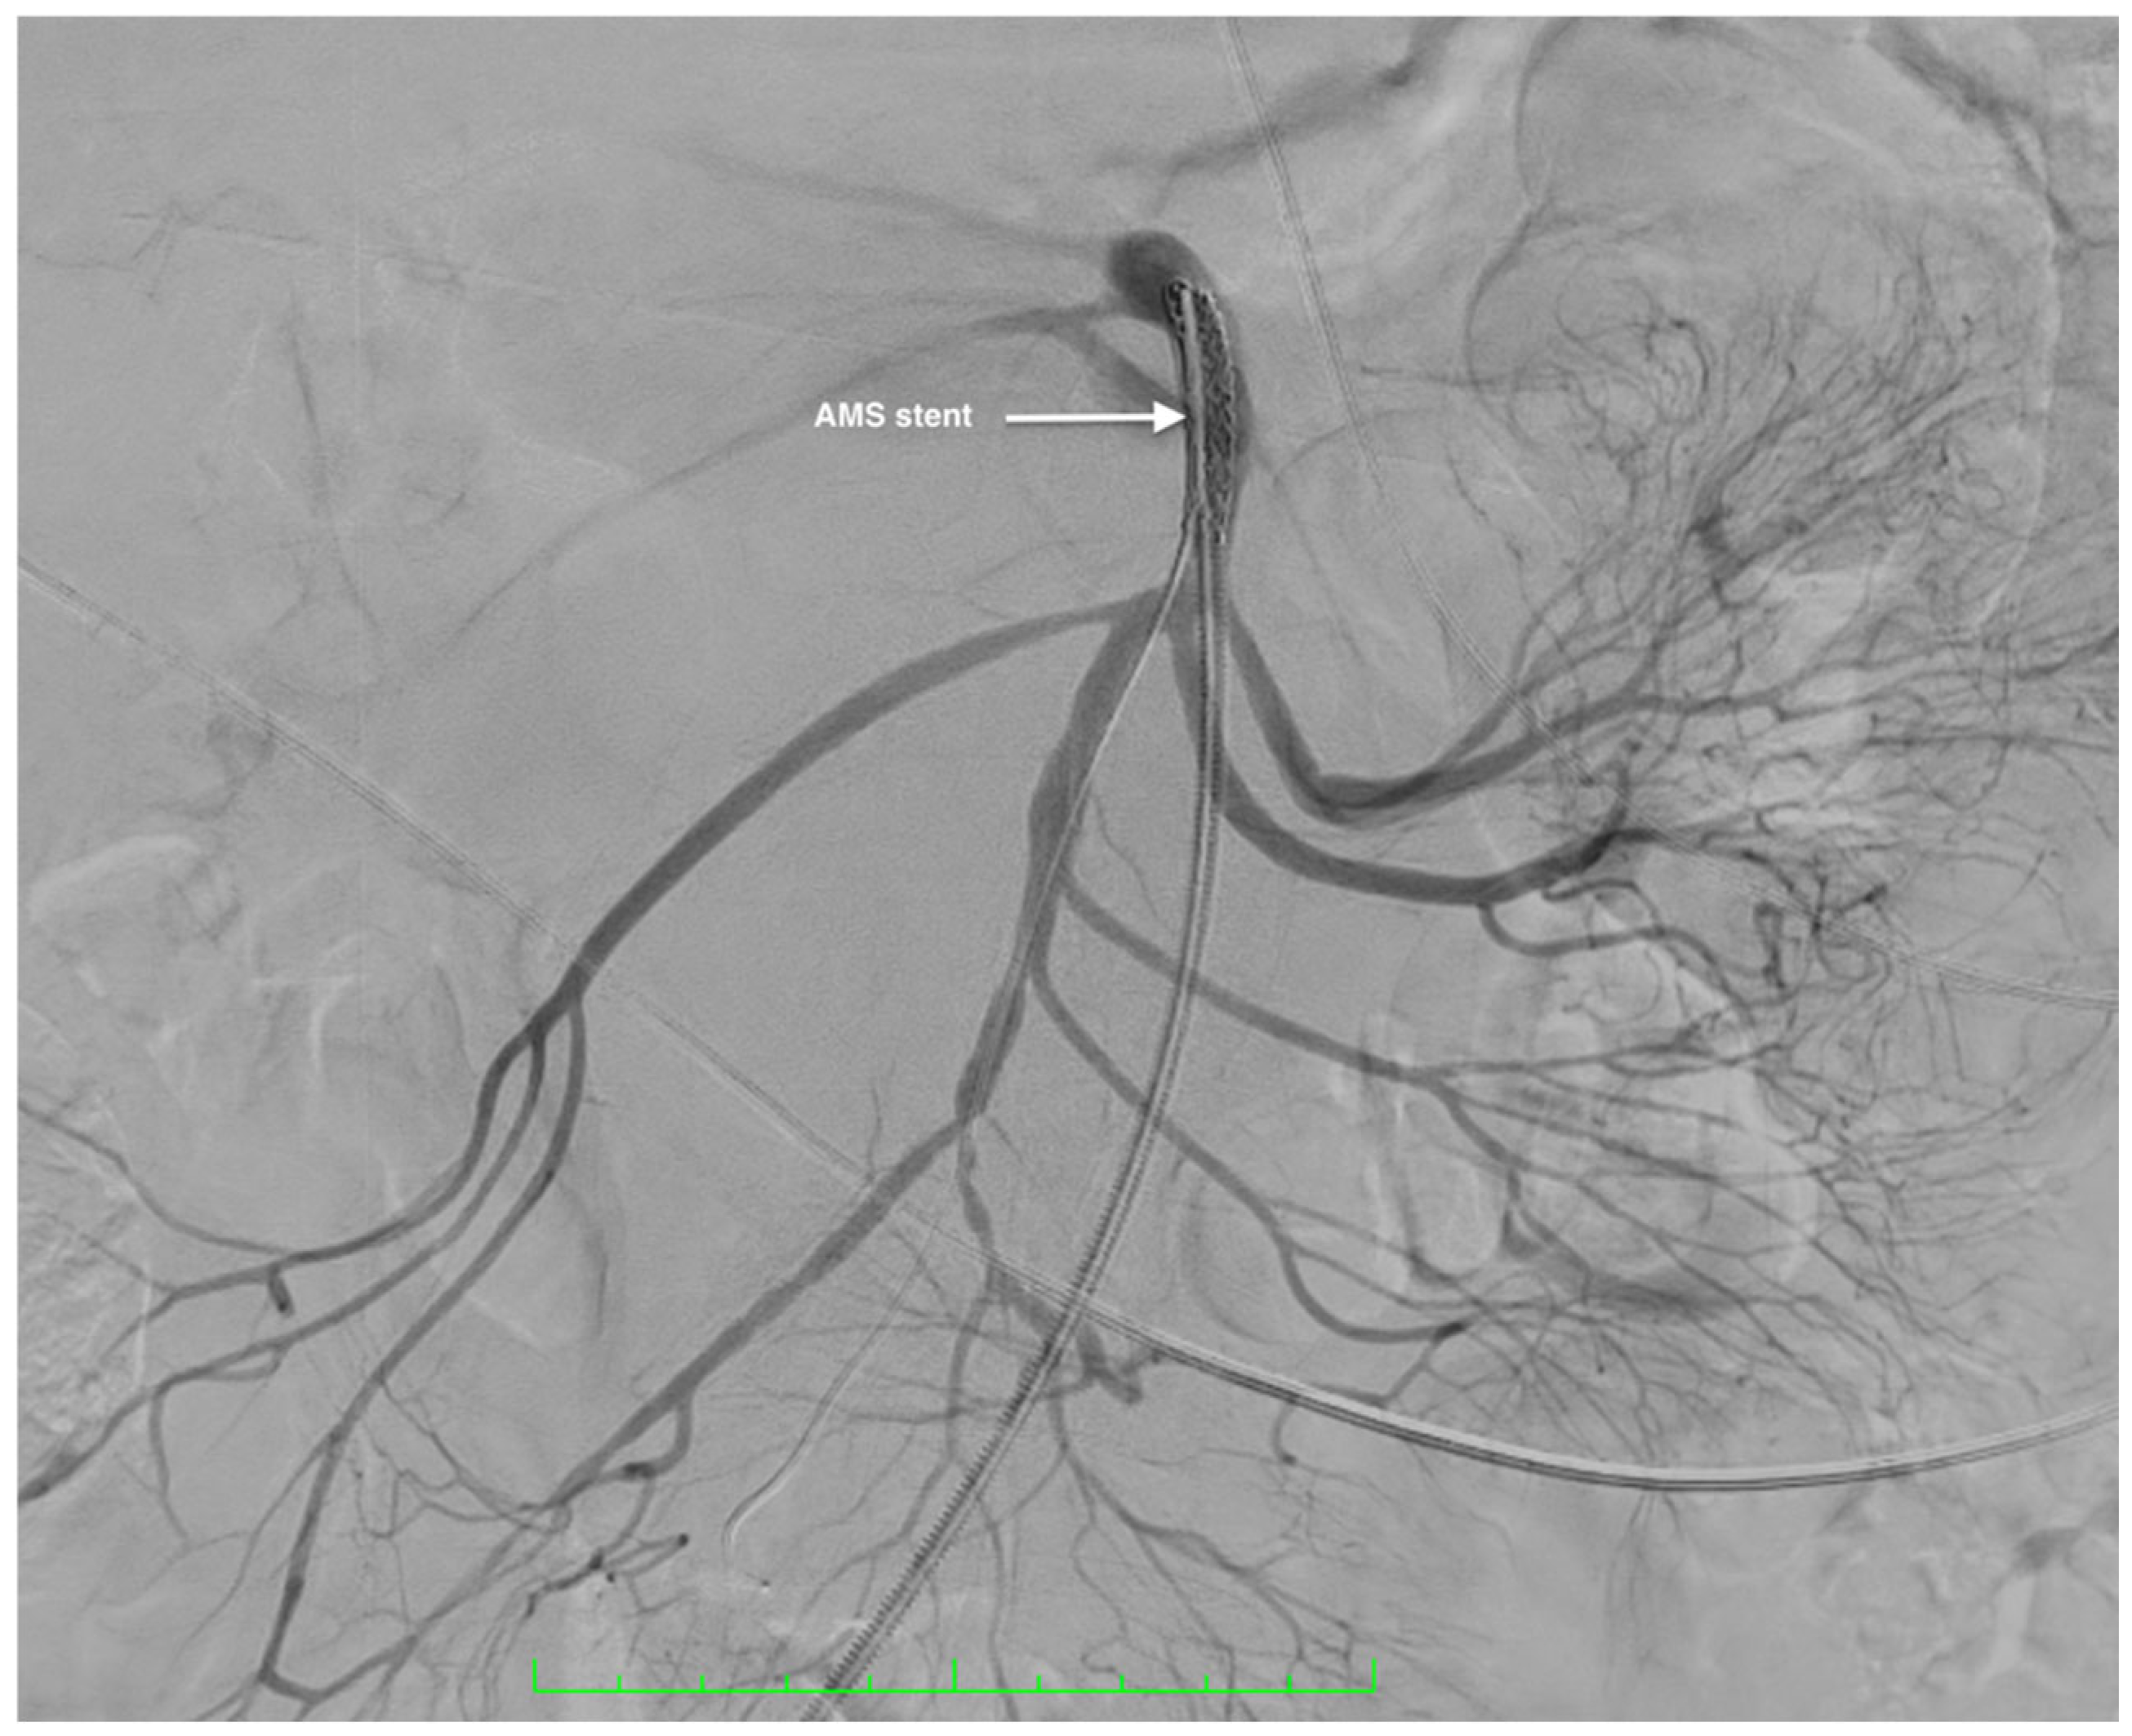

Management of a Rare Case of Superior Mesenteric Artery Aneurysm Associated with a Pancreatic Cyst Complicated by Acute Rupture: A Case Report and Review of Literature

2. Case Report

Surgical Technique